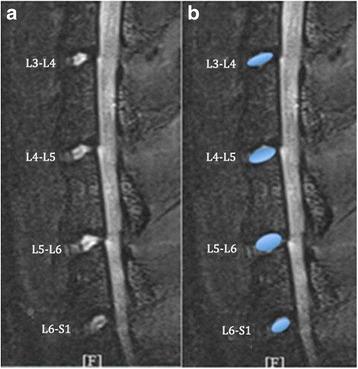

T2-weighted images revealed that with aging, the shape of L3-L4, L4-L5, L5-L6, and L6-S1 nucleus pulposus (NP) became irregular, while the mean areas, signal intensities, and T2 values of the NP were significantly decreased. Each of the observed disc changes demonstrated a progressive increase in phase during 2-min scout scans. Post-contrast MRI showed impaired endplate nutritional diffusion to the disc with aging, enhancement was significantly greater in young animals than in old animals. Endplate calcification or sclerosis was histologically confirmed; histologic score was correlated with the age. We found the histological score of the endplate negatively corresponded to the DCE-MRI results.

T2加权图像显示,随着年龄增长,L3-L4、L4-L5、L5-L6和L6-S1椎间盘髓核(NP)的形状变得不规则,而NP的平均面积、信号强度和T2值显著降低。在2分钟的定位扫描过程中,观察到的每个椎间盘变化均显示出相位的逐渐增加。造影后MRI显示,随着年龄增长,终板向椎间盘的营养扩散受损,年轻动物的增强明显大于老年动物。组织学证实存在终板钙化或硬化;组织学评分与年龄相关。我们发现终板的组织学评分与DCE-MRI结果呈负相关。